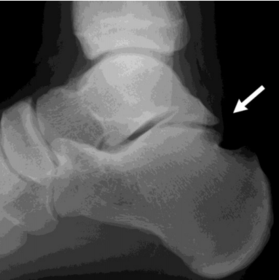

| What disease is this? What does the arrow indicate? | Rheumatoid arthritis. Arrow = Bone erosion secondary to inflammation of retrocalcaneal bursa. |